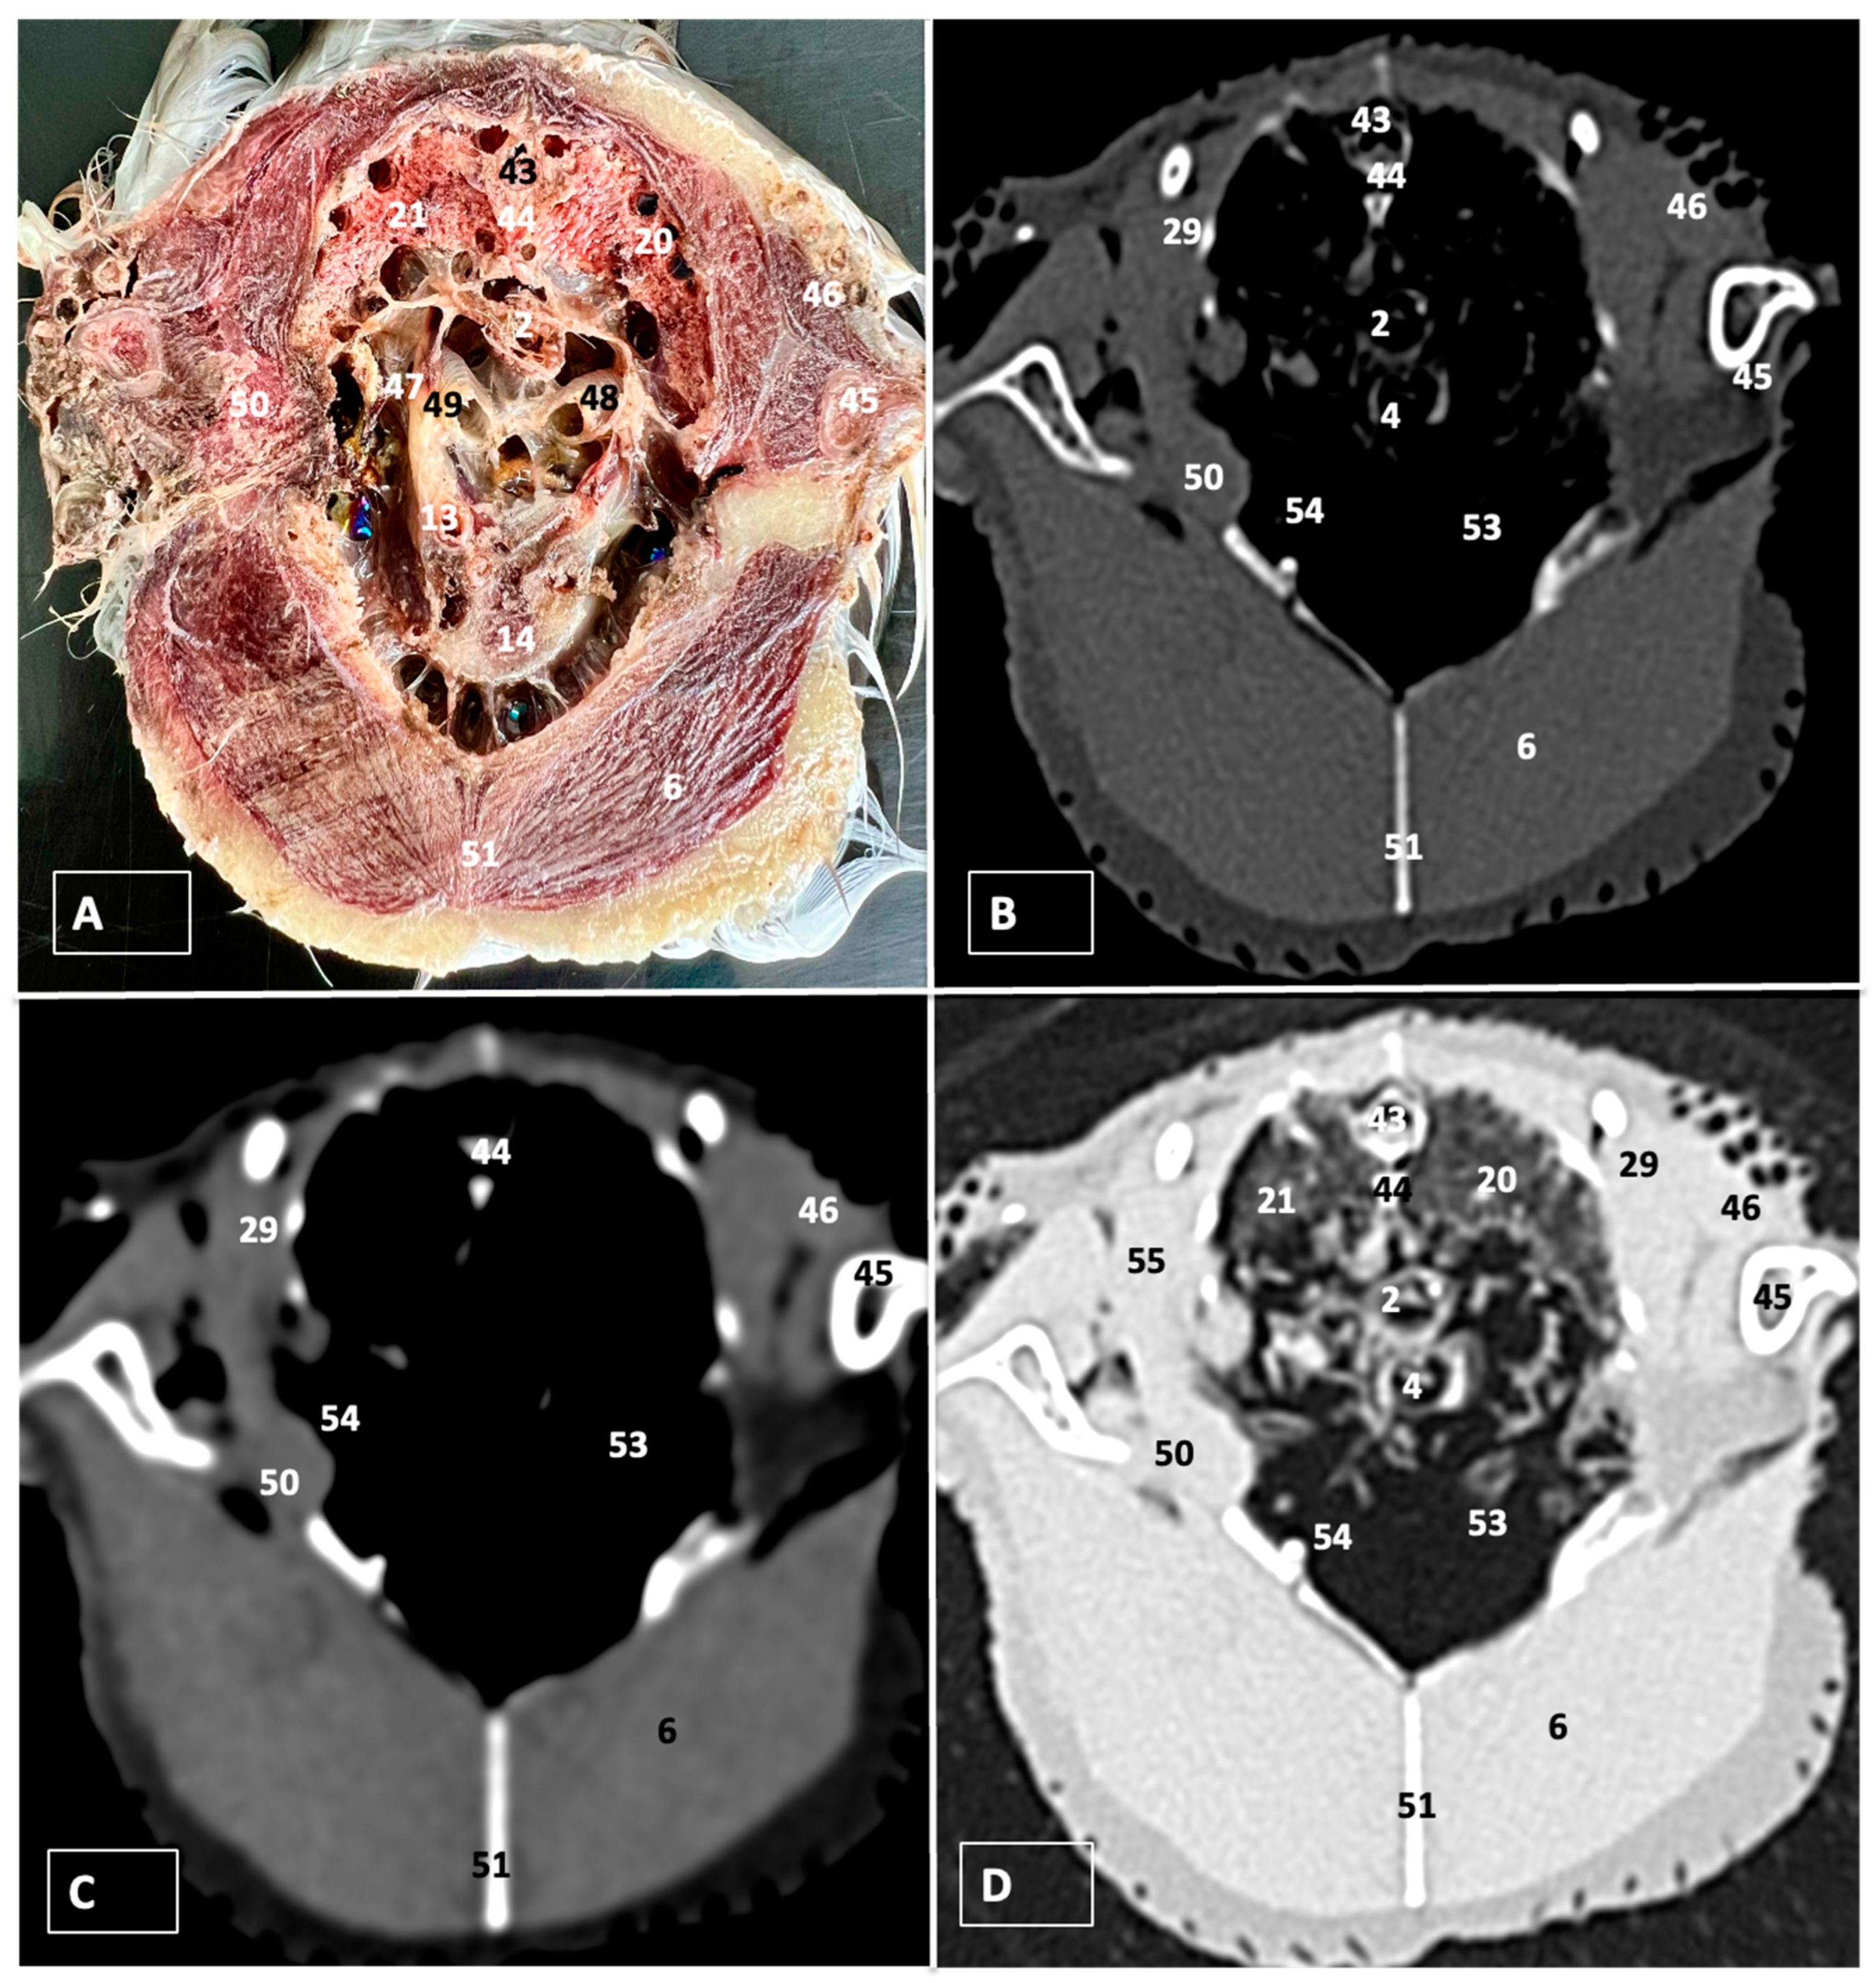

3. Results

3.1. Anatomical Dissections and Cross-Sections

3.2. Computed Tomography Images